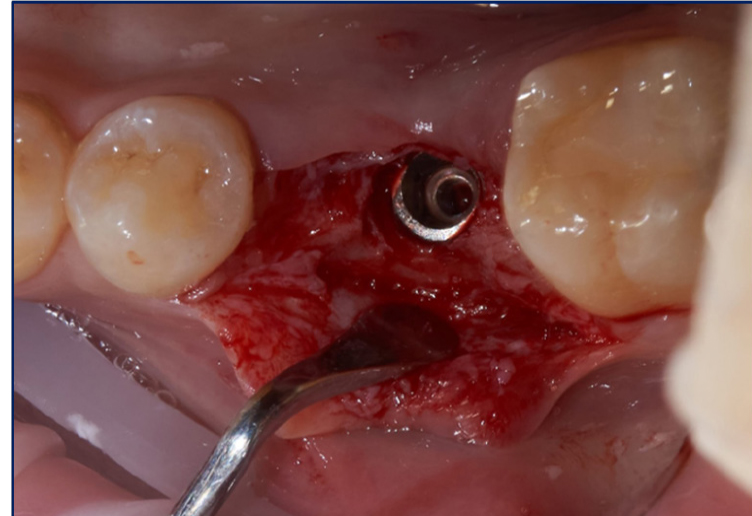

На базе стоматологической поликлиники ВолгГМУ было реализовано оперативное лечение и последующее наблюдение и анализ клинического случая по замещению включенного дефекта зубного ряда с использованием конструкции с опорой на дентальный имплантат. За 4 месяца до планируемой имплантации пациенту М., 25 лет, было произведено атравматичное удаление зуба 3.6, ввиду периапикального деструктивного процесса, потери ферулла твердых тканей маргинальной зоны. В области лунки был помещен коллагеновый матрикс Parasorb, использованы наводящие Z-образные швы Гликолон 5.0. Перед установкой дентального имплантата было визуализировано проявление дефицита и коллапса мягких тканей в участке адентии при удовлетворительных костных условиях для проведения имплантации (рис. 1).

В ходе операции был реализован комбинированный лоскут, с расщепленной частью в апроксимальных и апикальных участках, с целью создания оптимальных условий для кератинизации, реваскуляризации и созревания используемого соединительно-тканного трансплантата. Платформа дентального имплантата (Osstem 4,5/10) спозиционирована субкрестально на 3 мм с целью компенсации вертикального дефицита мягких тканей для формирования биологической ширины (рис. 2).